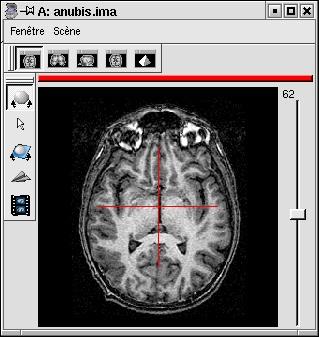

- Optionally, any point of the left hemisphere. Specifying this point is not mandatory, it is only useful to detect a possible orientation problem on the input image. Be careful, axial and coronal views in Anatomist are in radiological convention by default (left and right are flipped).

Point of the left hemisphere (on the right on axial slices displayed in radiological convention):